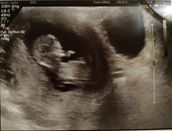

Gestern war dann endlich der Termin für "Baby-TV". Der Termin war erst halb 5, ich war ab Mittags doch sehr hibbelig. Ich konnte mir unter Baby-TV nichts vorstellen.

Doch wenn du die Fruchthöhle siehst und da drinne was pocht ganz schnell, dann weiß man was Baby-TV ist.

Für mich stand in diesem Moment kourz die Welt still. Es war irgendwie überwältigend.

Unbeschreiblich!